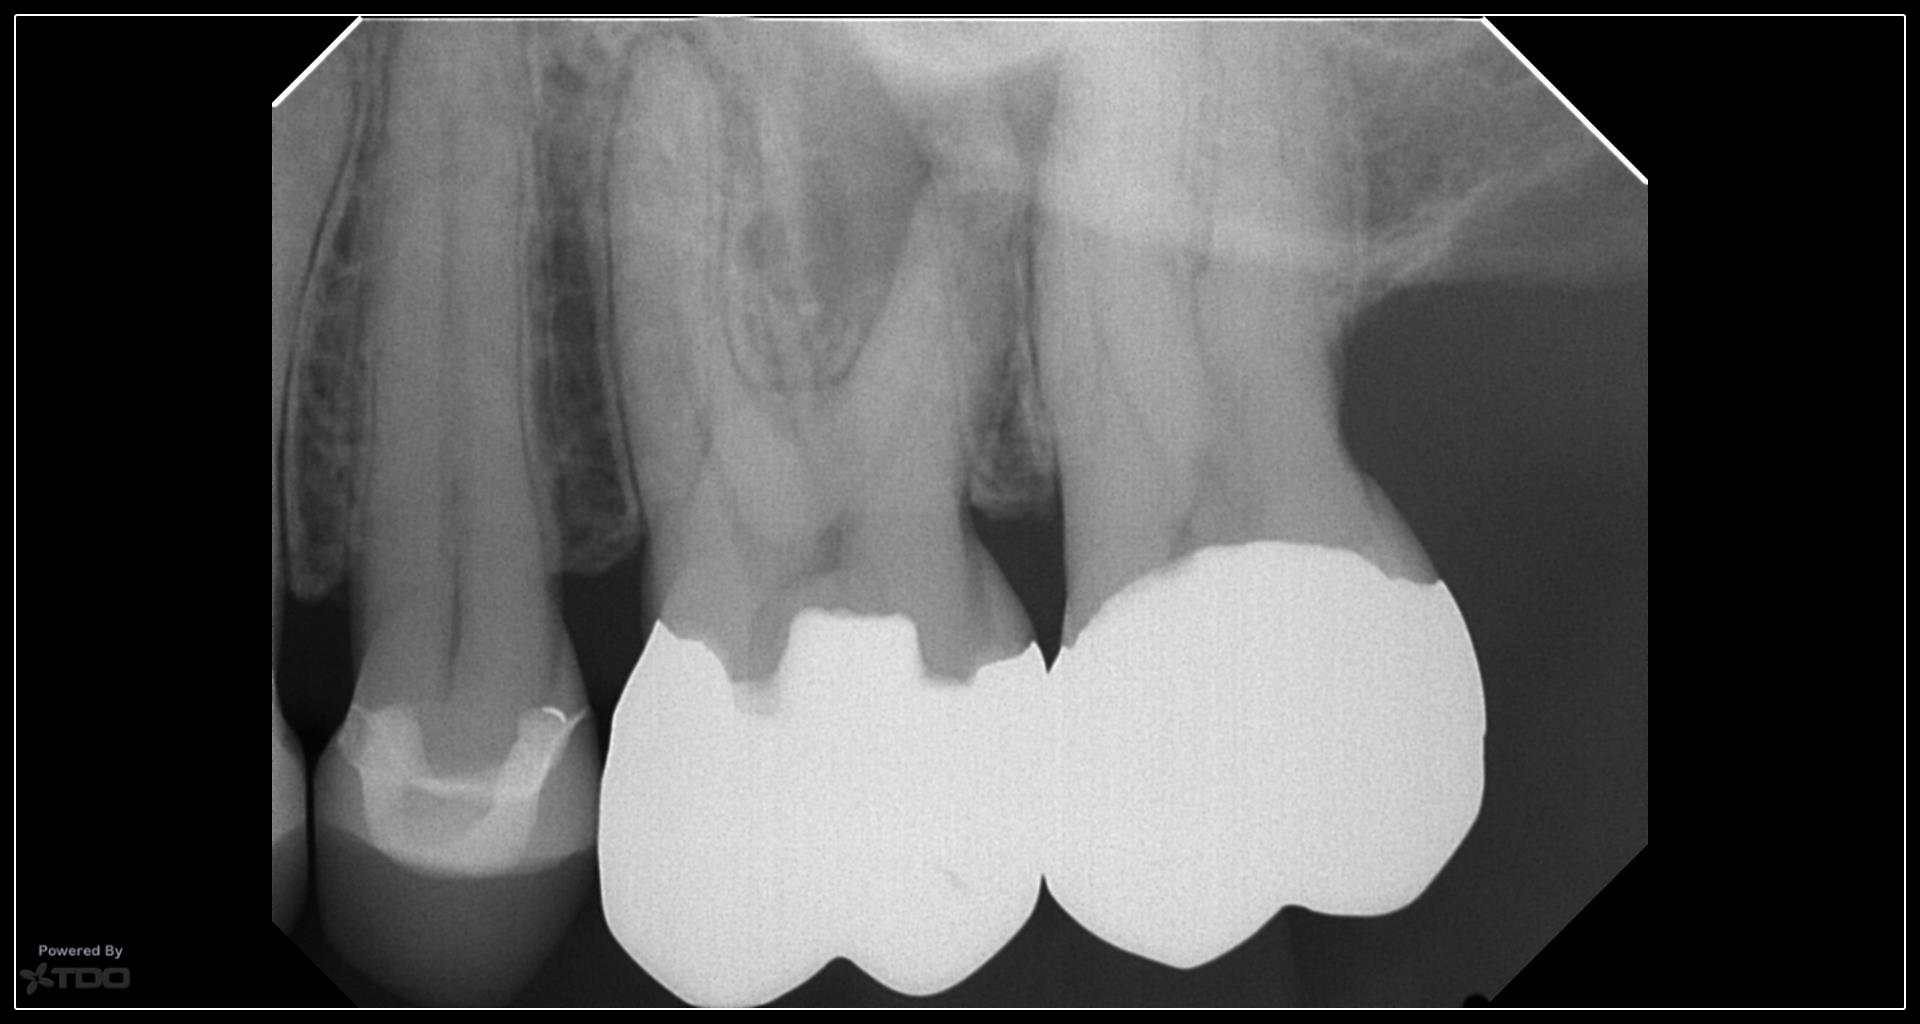

Scheduled for a GW…then I took a CBCT…….. No way, Jose……. Tried to minimize the access just for practice…… not even close to Nishan territory but still trying….. gbc